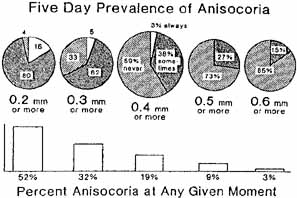

of the tumor. Spine 28(2):E33, 2003 161. Gilmer-Hill HS, Kline DG: Neurogenic tumors of the cervical vagus nerve: Report of four cases and

review of the literature. Neurosurgery 46(6):1498, 2000 162. Moukheiber AK, Nicollas R, Roman S, et al: Primary pediatric neuroblastic tumors of the neck. J Pediatr Otorhinolaryngol 60(2):155, 2001 163. George ND, Gonzalez G, Hoyt CS: Does Horner's syndrome in infancy require investigation. Br J Ophthalmol 82(1):51, 1998 164. Birchler MT, Landau K, Went PT, Stoeckli SJ: Paraganglioma of the cervical sympathetic trunk. Ann Otol Rhinol Laryngol 111(12 Pt 1):1087, 2002 165. Moyer JS, Bradford CR: Sympathetic paraganglioma as an unusual cause of Horner's syndrome. Head Neck 23(4):338, 2001 166. Leone A, Cerase A, Tarquini E, Mule A: Chordoma of the low cervical spine presenting with Horner's syndrome. Eur Radiol Suppl 4:S43, 2002 167. Bell RL, Atweh N, Ivy ME, Possenti PA-C: Traumatic and iatrogenic Horner syndrome: Case reports and review of literature. J Trauma 51(2):400, 2001 168. Ringer AJ, Fessler RD, Qureshi AI, et al: Horner's syndrome after carotid artery stenting: Case report. Surg Neurol 54(6):439, 2000 169. Taskapan H, Oymak O, Dogukan A, Utas C: Horner's syndrome secondary to internal jugular catheterization. Clin Nephrol 56(1):78, 2001 170. Perry C, James D, Wixon C, et al: Horner's syndrome after carotid endarterectomy: A case report. Vasc Surg 35(4):325, 2001 171. Kerrison JB, Biousse V, Newman NJ: Isolated Horner's syndrome and syringomyelia. J Neurol Neurosurg Psychiatry 69(1):131, 2000 172. Parkinson D: Bernard Mitchell, Horner's syndrome and others? Surg Neurol 11:221, 1979 173. Abad JM, Alvarez F, Munoz J, et al: Un sindrome neurologico no reconocido: Paralisis del sexto par y sindrome

de Bernard Horner's debido a lesiones traumaticas intracavernosas. Rev Clin Esp 165:135, 1982 174. Gutman I, Levartovski S, Goldhammer Y, et al: Sixth nerve palsy and unilateral Horner's syndrome. Ophthalmology 93:913, 1986 175. Havelius ULF, Hindfelt B: Minor vessels leaving the extracranial internal carotid artery: Possible

clinical implications. Neuro-Ophthalmology 5:51, 1985 176. Grimson BS, Thompson HS: Raeder's syndrome: A clinical review. Surg Ophthalmol 24:199, 1980 177. Grimson BS, Thompson HS: Drug testing in Horner's syndrome. In: Glaser JS, Smith JL (eds): Neuro-Ophthalmology Symposium, vol 8. St Louis: CV Mosby, 1975:265–270 178. Giles CL, Henderson JW: Horner's syndrome: An analysis of 216 cases. Am J Ophthalmol 46:289, 1958 179. Grimson BS, Thompson HS: Horner's syndrome: Overall view of 120 cases. In: Thompson HS, Daroff RB, Frisen L, et al (eds): Topics in Neuro-Ophthalmology. Baltimore: Williams & Wilkins, 1979:151–156 180. Keane JR: Oculosympathetic paresis: Analysis of 100 hospitalized patients. Arch Neurol 36:13, 1979 181. Maloney WF, Younge BR, Moyer NJ: Evaluation of the causes and accuracy of pharmacologic localization in